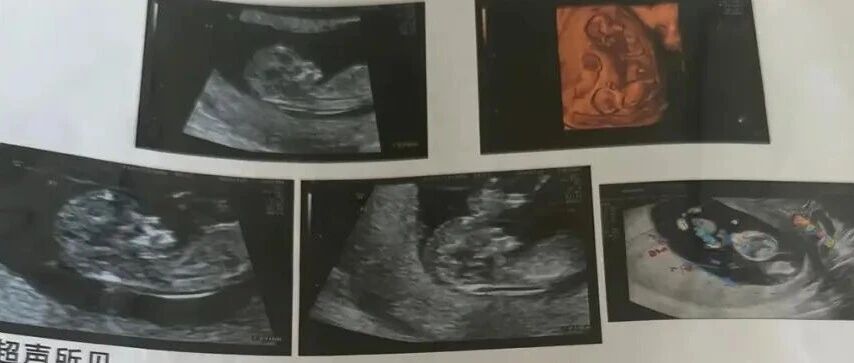

根据第四次产检彩超检查单结果,王女士的第四胎是无心畸胎(考虑反向动脉灌注序列征)。医生解释,她的第四胎虽然没有胎心,但血管与其他三个胎儿相连,由其他胎儿为其供血。如果同卵四胎正常发育,可能导致其他胎儿存在先天性心衰的症状。

沈阳市妇婴医院彩超显示同卵四胞胎。当事人供图